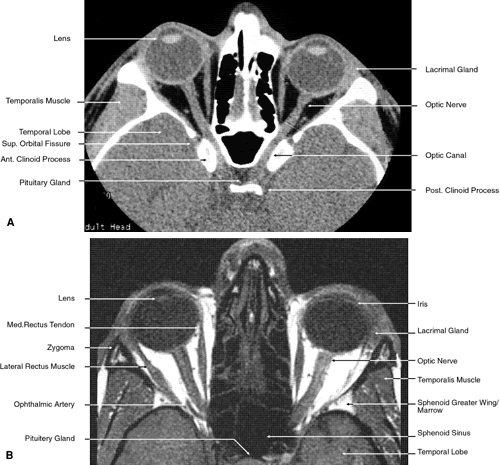

The globe is shown in Figure 12. The orbit and periorbital structures are shown in Figures 13 through 16, and the optic canal is shown in Figures 17 through 26. The cavernous sinus and optic chiasm are shown in Figures 27 and 28, and the posterior visual pathway and cranial nerves are shown in Figures 29 through 33.

Fig. 23. Axial images at the level of midorbit. A. Computed tomography scan. B. T1-weighted magnetic resonance imaging.

Fig. 24. Axial images at the level of superior orbit. A. Computed tomography scan. B. T1-weighted magnetic resonance imaging.

Fig. 3. Axial computed tomography scan of the orbital apex and optic canal.